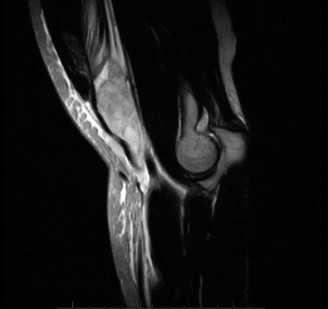

While plain films confirm the presence of osseous reactive changes, Magnetic Resonance Imaging (MRI) is indispensable for evaluating the articular cartilage, the integrity of the UCL, and the presence of occult loose bodies. A high-resolution MRI, preferably an MR Arthrogram (MRA) if subtle UCL pathology is suspected, provides a comprehensive map of the elbow's soft tissue envelope.

In this case, the MRI demonstrates focal chondromalacia and subchondral edema at the posteromedial olecranon tip and the corresponding medial wall of the olecranon fossa—the classic "kissing lesion" of VEO. Crucially, the anterior bundle of the UCL appears continuous and intact, with no evidence of high-grade partial tearing, T-sign (contrast leakage beneath the distal insertion), or severe attenuation. The flexor-pronator mass and the ECRB origin are pristine.